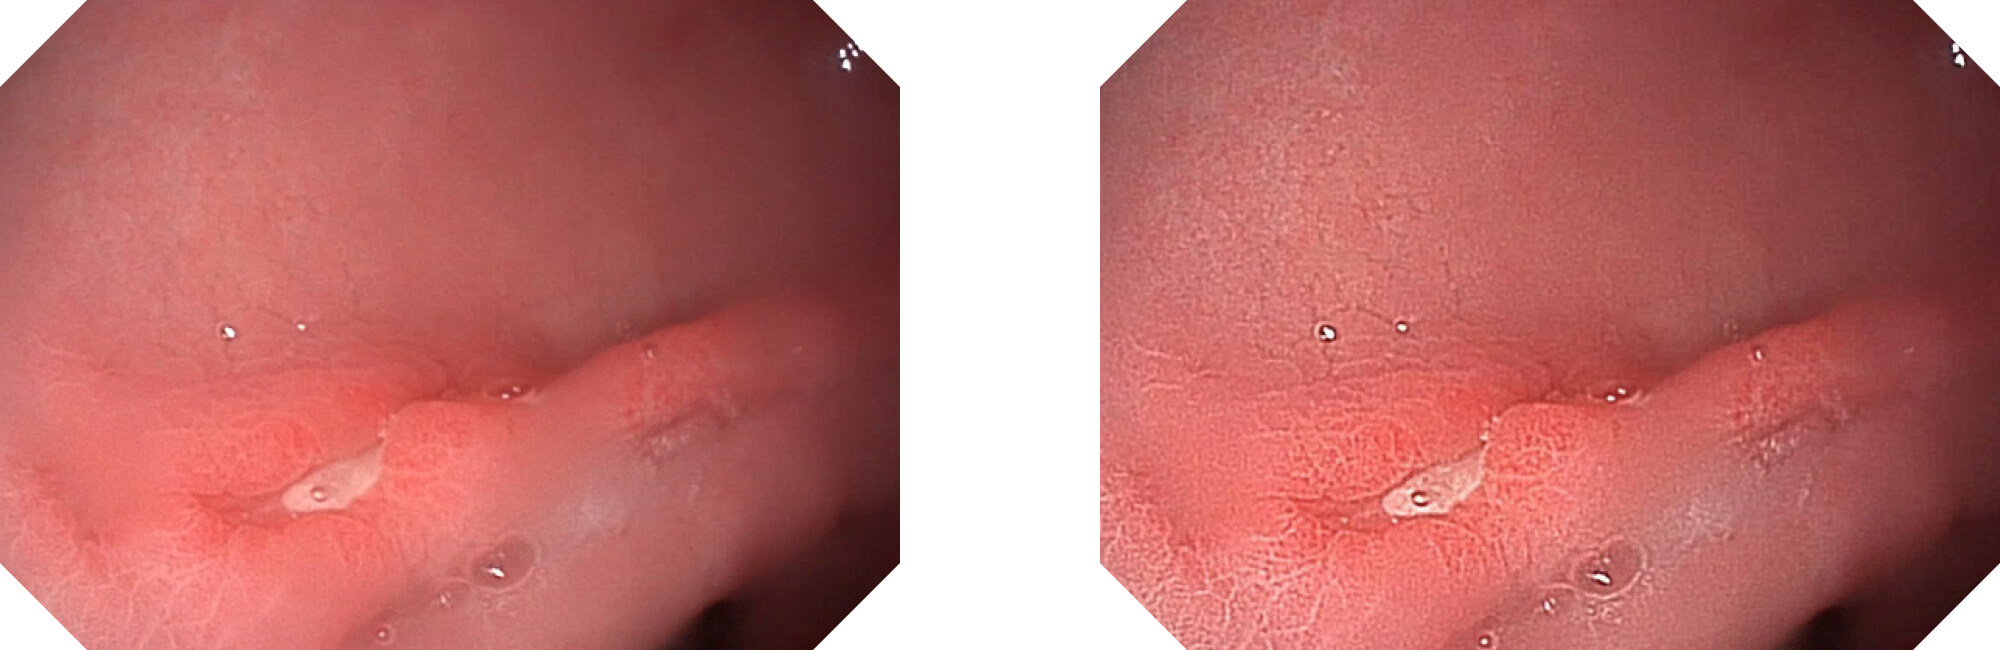

清晰视界,诊断胸有成竹

高清数字信号结合构造强调和色彩增强,多重图像处理技术能让每一个图像都清晰可见。

• 构造强调

• 色彩增强

• 电子放大